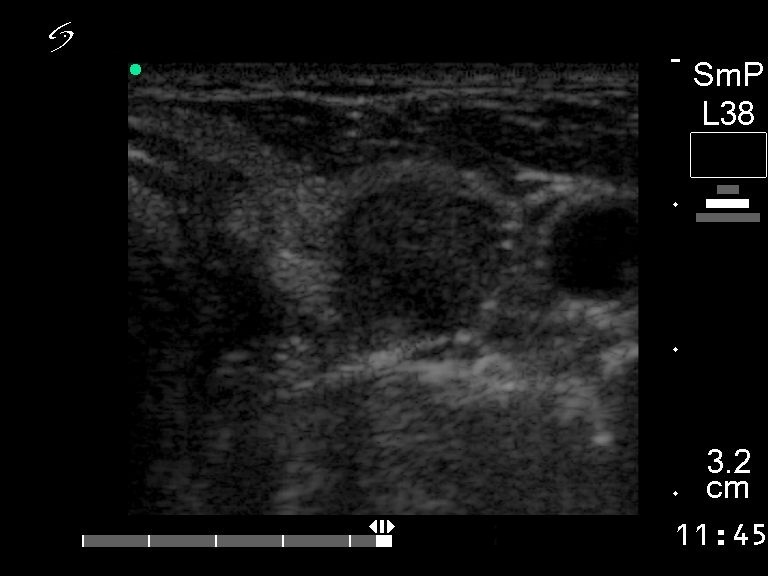

Ultrasonography. There was a solitary hypoechogenic nodule in the left lobe.